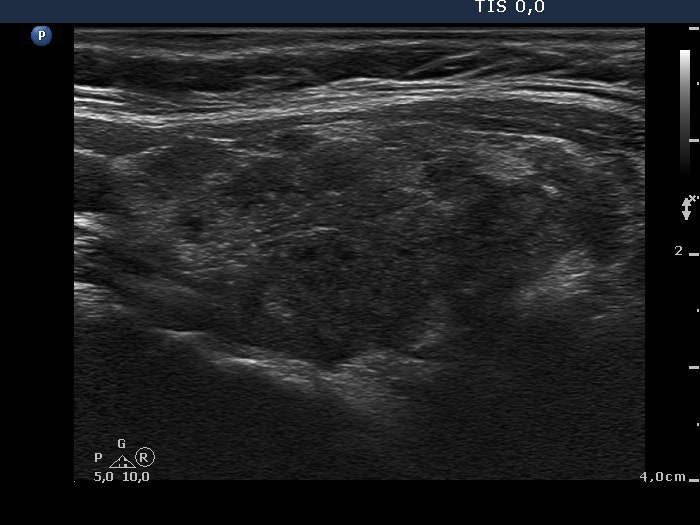

Case cons100_010 (ultrasonographic picture 3)

Right lobe, another longitudinal scan. This is a typical ultrasound presentation of lymphocytic thyroiditis: great proportion of the lobe is hypoechogenic while the small discrete echonormal areas correspond to intact parts of the lobe not or only less influenced by thyroiditis.